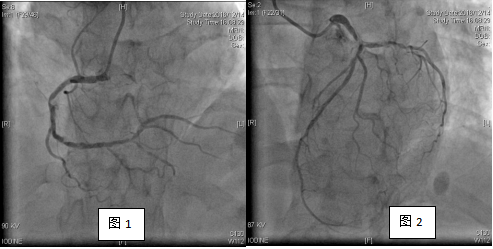

造影结果如图(1-2):

(可见左主干末端严重狭窄,前降支及回旋支开口严重狭窄,第一对角支开口80%狭窄,右冠脉弥漫性病变,严重段90%狭窄,后降支弥漫性病变。)